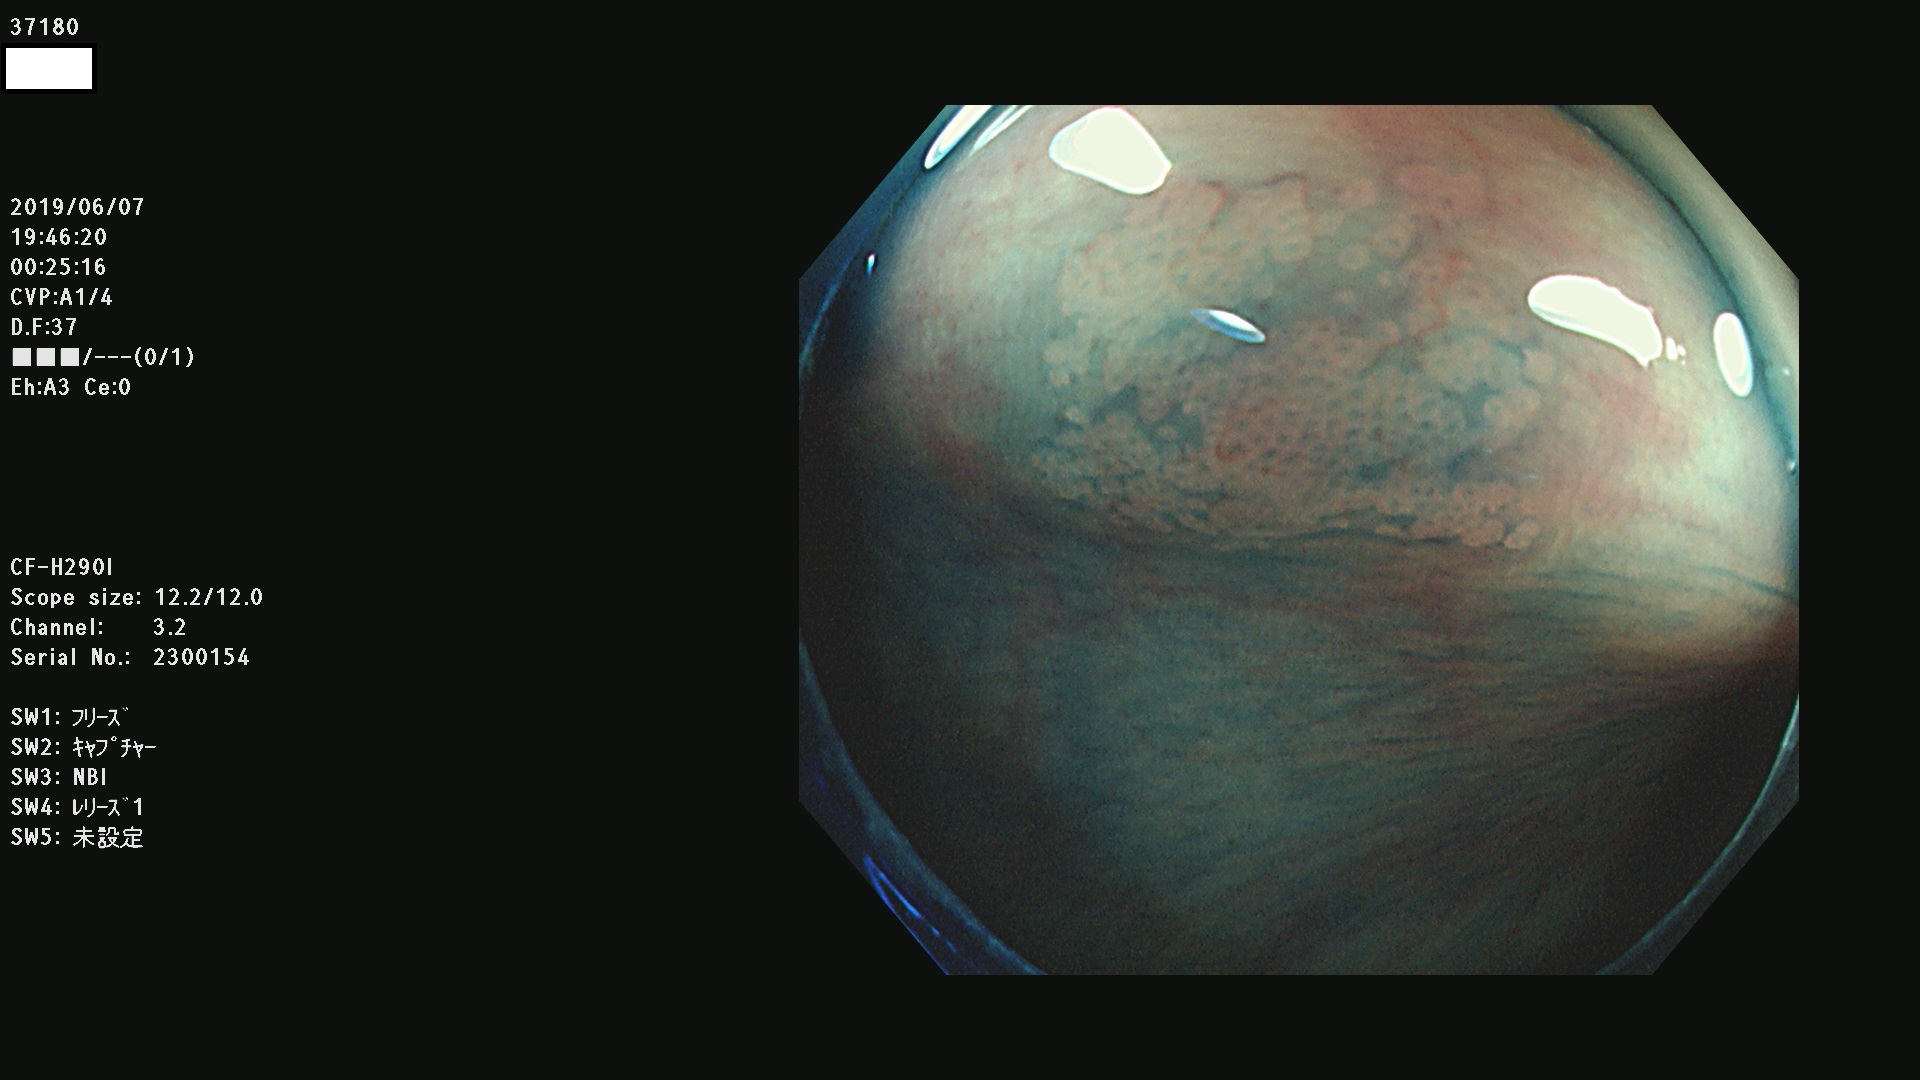

37100 37101 37102 37104 37106 37108 37110 37111 37112 37113 37115 37118(SSAPのみ) 37120 37122 37123 37124 37127(SSAPのみ) 37128(SSAPのみ) 37131 37132 37133 37134 37135 37139 37141 37142 37143 37144(SSAPのみ) 37145 37147(SSAPのみ) 37148 37149 37150 37153 37154 37157 37159 37161 37162 37163 37164 37165 37166 37167 37168 37169 37170 37171 37172 37173 37175(SSAPのみ) 37176 37177 37178 37180(SSAPのみ) 37181 37184 37185 37186 37187 37188 37189 37190 37192 37194 37197 37198

発見困難で危険性の高い平坦型病変(上記100名より抽出)